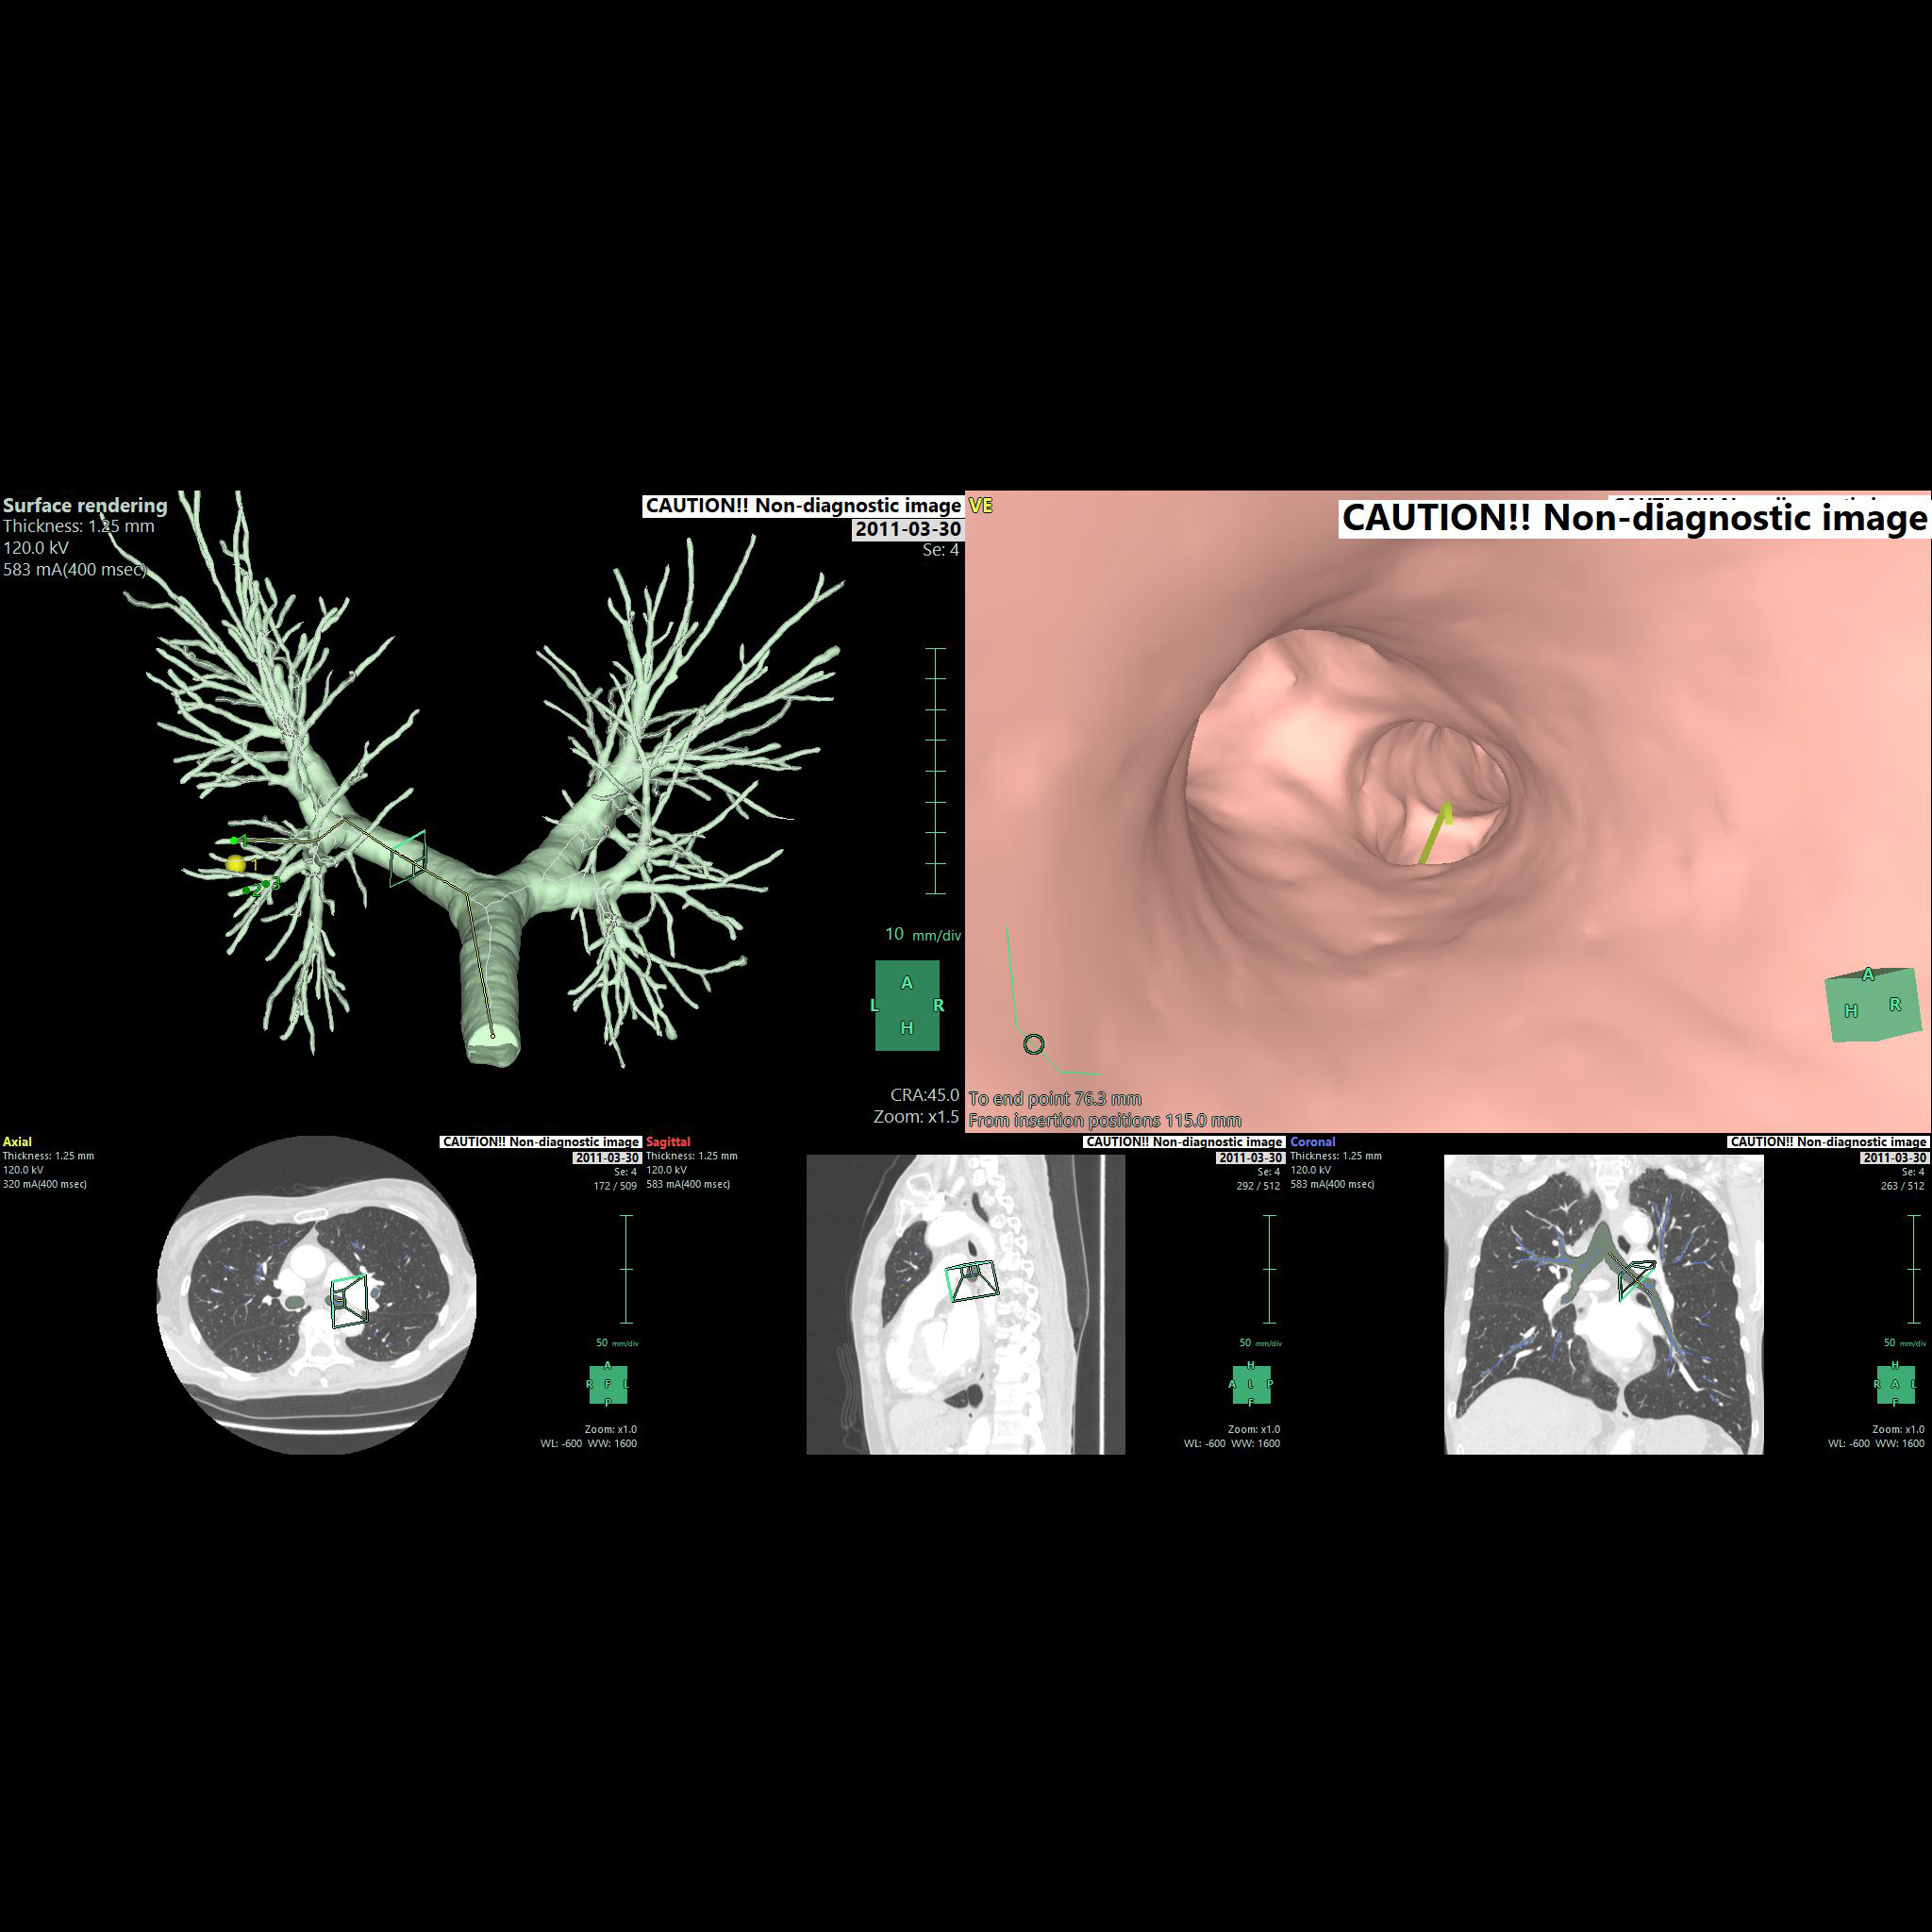

• - CT image를 사용하여 nodule까지의 path를 구성하고 관찰할 수 있습니다.

• - Bronchus의 직경 End-point부터 Nodule 까지의 거리 등을 확인하며 가상 내시경을 진행할 수 있습니다.